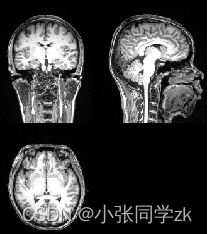

使用ITK中的itk::MedianImageFilter类可以实现医学图像的中值滤波,此类通过SizeType()函数设置每个维的邻域大小来实现滤波功能,如图2.8.23所示。

图2.8.23 MRI图像的中值滤波